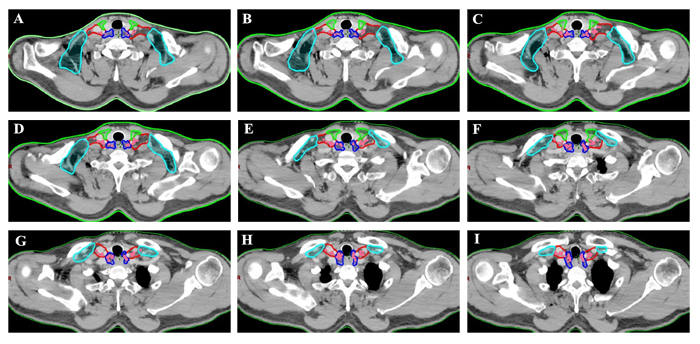

In addition, we analyzed the distribution pattern of lower cervical LNM in these patients. In the entire cohort, 151 nodes were considered to be metastatic in the lower cervical region of those patients. The median number of positive nodes was 2 (ranged, 1-5). The anatomic distribution of metastatic nodes was 4 of 151 (2.6%) in group I, 68 of 151(45%) in group II, 77 of 151 nodes (51%) in group III, and 2 of 151 (1.4%) in group IV, respectively. The distribution of 151 lower cervical nodes in different subgroup regions were listed in Table 2, and axial images demonstrating the anatomic distribution of all of these lymph nodes was shown in Figure 2.

Figure 2: Regions encircled with green line are SubgroupI, those with dark blue line are SubgroupII, those with red line are Subgroup III and those with bright blue line are SubgroupIV. Location of lower cervical metastases at presentation. Pink coloration indicates location of nodal disease in patients with lower cervical metastasis.

All mapped LN locations were individually reviewed and edited to most precisely represent the corresponding location on the original CT or PET/CT scan by 2 radiologist (Y.L, Y.H) and by 2 radiation oncologists (X.W, J.Y). The nodes were considered to be clinical metastatic in the lower cervical region for all patients were registered by hand drawings from the original CT image onto the template CT image according to methods previously described. [20, 31, 32] The volumetric center of each lymph node was identified and used for mapped on the template images to the best of our ability, and then a volume probability atlas of those nodes was generated. Figure 2 illustrates our LN mapping result for a representative patient. As seen in the atlas, it was displayed on the template image for a visual representation of the density of distribution. Our findings may provide a reference to improve target volume definition in esophageal cancer patients referred for definitive CRT.